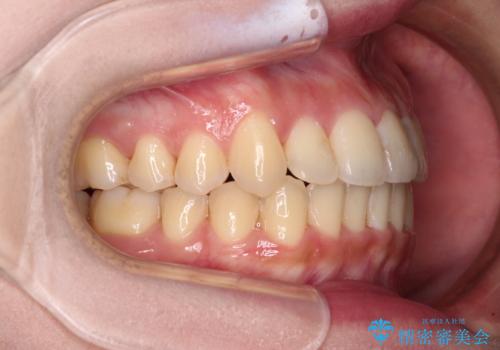

- 前歯のデコボコを気にして来院された患者様です。

上顎右側犬歯が八重歯になっており、それによって奥歯が前方に移動しているため、右側の咬み合わせの改善が必要と判断されました。

より治療を速やかに行うため、上顎右側にアンカースクリューを使用し、目標としていた1年半ほどで治療を終えることができました。